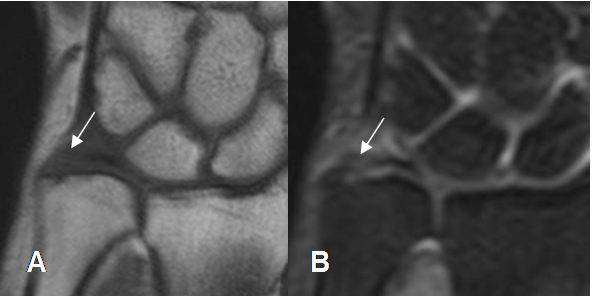

La presencia de líquido rodeando la articulación radioulnar distal, es un importante signo secundario de ruptura. (6). (Fig 78).

Fig 78. Ruptura del FCT.

A: RM axial en T2 y B: RM coronal en STIR. Presencia de líquido en la articulación radioulnar distal, por ruptura no mostrada del FCT.